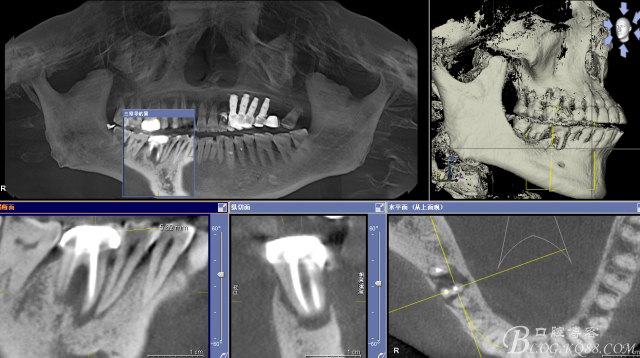

CT可見根管內(nèi)有白色顯影物和根周較大暗影

從根管影像看治療還是不錯(cuò)的,

懷疑牙根微裂,

所以建議患者手術(shù)探查